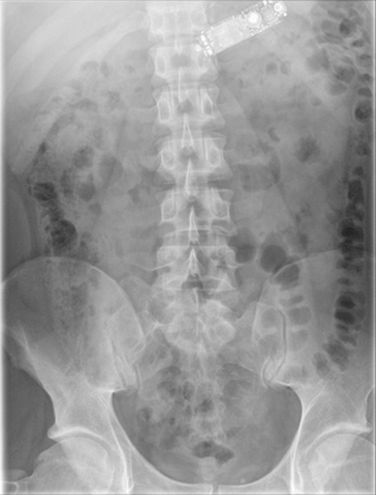

Mężczyzna osadzony w więzieniu w Dublinie trafił do szpitala w Tallaght, bo źle się poczuł. Wyniki badania rentgenowskiego wprawiły personel medyczny w osłupienie.

Wydaje się to niemożliwe, jednak 29-latek zadziwił lekarzy. Więzień zdołał przełknąć telefon komórkowy w całości! Osadzony poczuł się źle i gdy wymioty nie ustępowały przez kilka godzin, został zabrany do szpitala. Gdy przyznał się, co zrobił, lekarze byli zaskoczeni.

Medycy bezskutecznie próbowali wyłowić telefon. Za pomocą specjalnych chwytaków dołączonych do kamerki przez gardło dotarli do żołądka. Mężczyzna został zabrany na salę operacyjną. Szczegóły zostały opisane w międzynarodowym czasopismie dokumentującym przypadki chirurgiczne.

Lekarze przeprowadzili laparotomię. Twierdzą, że to rzadki przypadek ze względu na rozmiary telefonu, choć połknięcie ciała obcego wśród więźniów zdarza się dosyć często.

Do końca nie jest jasne, jak i dlaczego więzień połknął telefon. Wiadomo tylko, że miał problemy ze zdrowiem psychicznym.